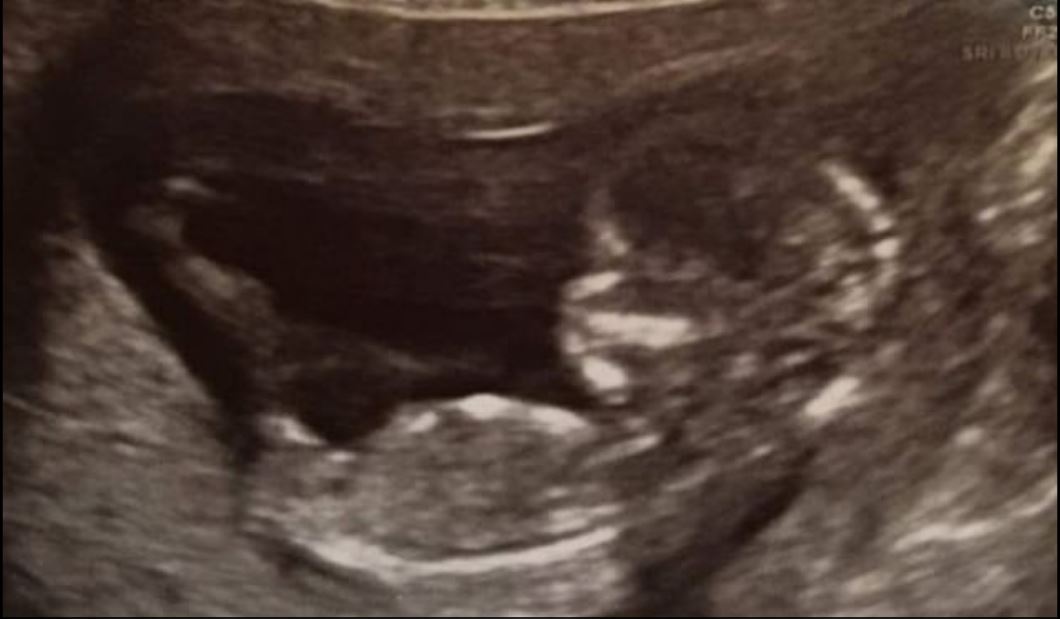

For this couple, life has been a bit too hard but in the end, they had their happy ending. The couple had 13 miscarriages and had lost all hopes of ever getting pregnant but they did get pregnant and welcomed a baby girl in the world.

35 years old Laura Worsley, had lost 13 babies. 11 miscarriages happened when she was in her first trimester and 2 of her miscarriages happened at 20 and 17 weeks.

The medication worked for them and they gave birth to a beautiful little baby girl named Ivy. She is now 9 months old.